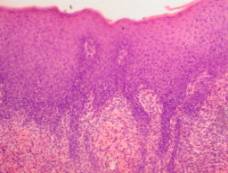

and discussion. As we can see in studies of intact rats, epidermis developed

well, consists of 3-5 rows of cells. We differentiated in it: one row of basal

cells, 1-3 rows of thorny cells, one or rarely two rows of granular cells and

the stratum corneum, which consists of fluffy corneal plates. Derma is wide

with compact bundles of collagen fibers with a few thin-walled blood vessels. Cell

saturation dermis is mild (lymphoid cells, fibroblasts). Epidermal-dermal

border is clear. Hair follicles are multiple, cut as extended and cross section

(pic.1а).

Рiс.

1 – intact rats skin (а). Positive control group rats skin: b – epidermis and

papillary dermis layer necrotized, demarcation shaft on the border with mesh

layer of the dermis; c – regenerated epidermis thickened under the crust, there

are visible signs are not sharply distinct spongiosis, fiber dermis are

swollen. d – hypertrophy of the epidermis, acanthosis, inflammatory reaction in

the dermis; f – inflammatory infiltrate around the hair follicle with the

destruction of the wall; g – narrowing of the capillary lumen, endothelial

proliferation, inflammatory reaction in the subcutaneous tissue.

Hematoxylin-eosin. х 100.

On 7th

day after applying crucial dose DNCB in all control pathology rats we found a

spreading skin destructions. Epidermis is deformed on this parts, often it

looks like amorphous mass, which densely infiltrated a cellular detritus, macrophages.

Collagen fibers are homogenized in papillary layer of the dermis, strongly

eosinophilic, epithelial cells of hair follicles and sheaths are in the

necrosis. There is visible demarcation shaft some places among the crust and

saved part of the dermis (pic. 1b). Often

crust extends far beyond the damage and covers (peels tightly or partially)

thickened epithelial layer, in which we could see a mild distinct spongiosis

(intercellular edema in the thorny layer), vacuolar degeneration of

epidermocytes. The epithelium of hair follicles proliferates. Collagen matrix

is swollen in the dermis and moderate polymorphonuclear infiltrates are visible

around some hair follicles and blood vessels (pic. 1c). Probably it was the

regeneration of damaged during primary-contact reactions to allergen skin in

these areas at the time of the experiment.

Often epithelial layer hypertrophied on the skin, free from peel, we can incomplete keratinization, acanthosis, more expressive spongiosis. We observed in the dermis infiltrates of histiocytes, lymphocytes, macrophages, plasma cells (pic. 1d). Inflammatory cell infiltration was observed often and around hair follicles and combined with their sebaceous glands (epithelial cells of them are necrotic) and in subcutaneous tissue. We traced wall thickening by hypertrophy and hyperplasia of endothelial cells and pericapillary in mesh dermis capillaries, capillary lumen is diminished (pic. 1f,g). The morphological picture is characteristic ACD.